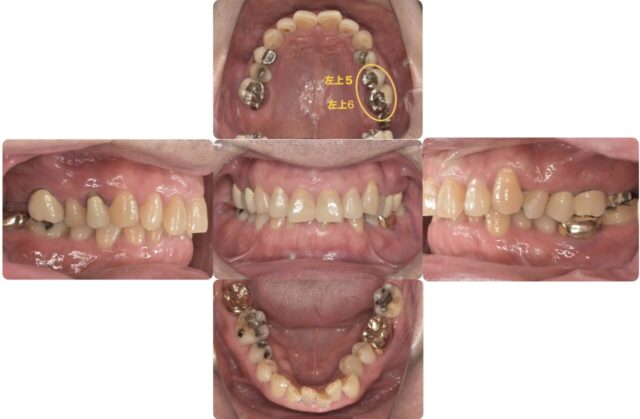

正面からのかみ合わせを見た時、下の歯がほとんど見えませんこれは「ディープバイト」と言ってよくない歯並びである不正咬合の一つです。

本来、人は上下の顎の前後運動により奥歯にかかる圧を抜いてバランスを保っています。しかしこのかみ合わせは前後に擦り合わせるスペースがないため、奥歯がずっと噛み合ったままの状態です。そのため、奥歯にばかり負担がかかり、ヒビが入ってきてしまったり、治療をして詰め物をしても取れてしまったりしてくるのです。これを治すにはかみ合わせのバランスを整える、つまり「矯正」が必要になります。